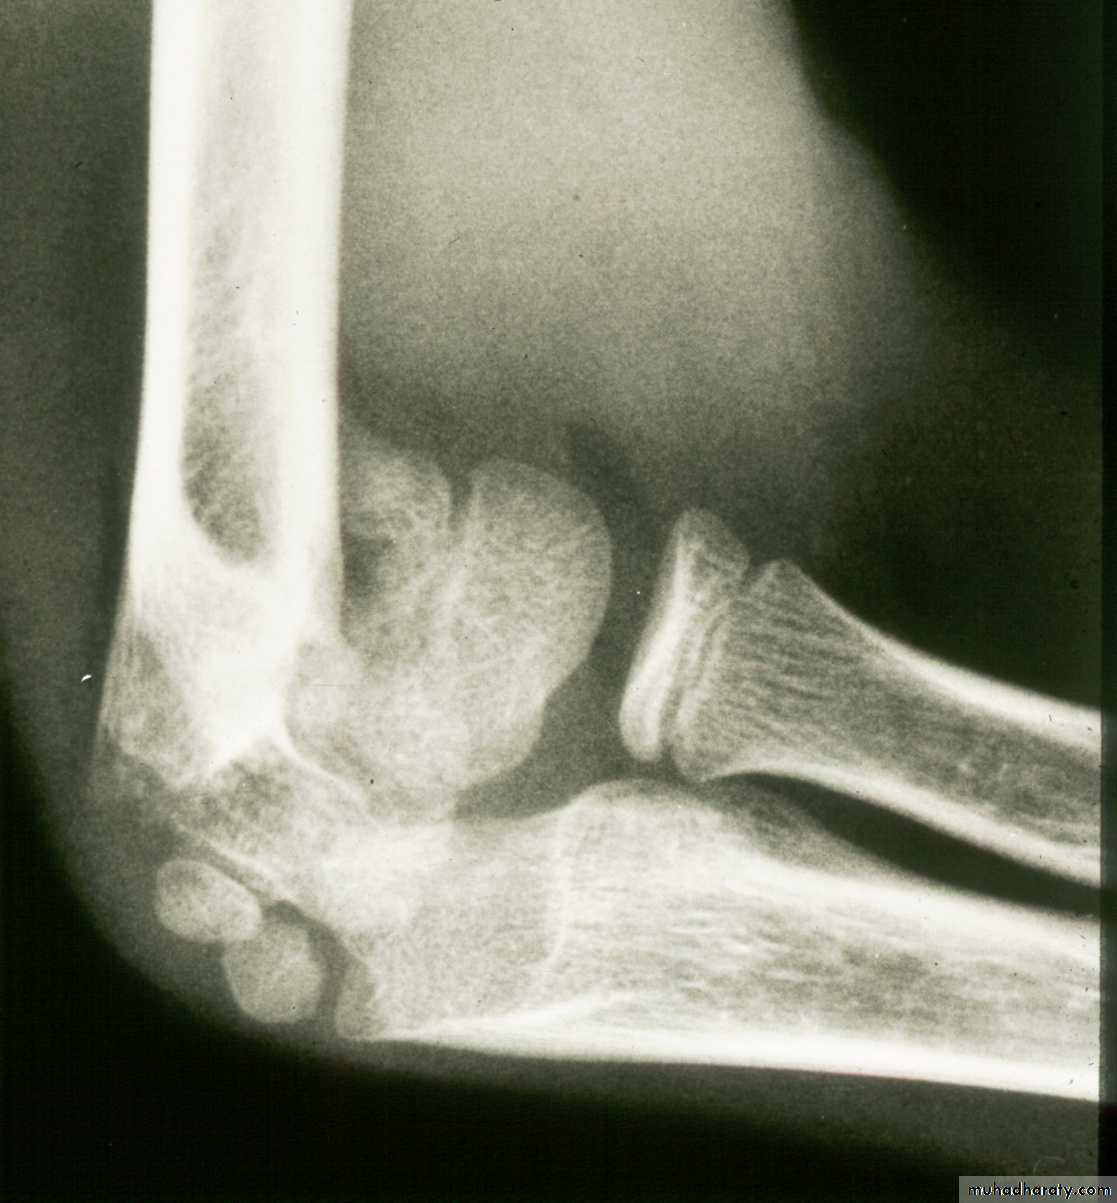

Five y.o. male with this fracture pattern

• Following obtaining a satisfactory closed reduction how do you propose to stabilize it?Multiple lateral pins

Stable ??Five y.o. male with this fracture pattern

• Following obtaining a satisfactory closed reduction how do you propose to stabilize it?

Medial-lateral

retrograde cross pinsDifficult and unstable